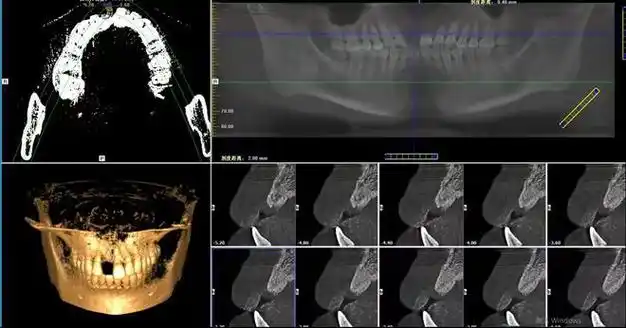

年轻人缺牙种植更不能拖|义齿|手术|牙齿|种植体|口腔疾病_网易订阅